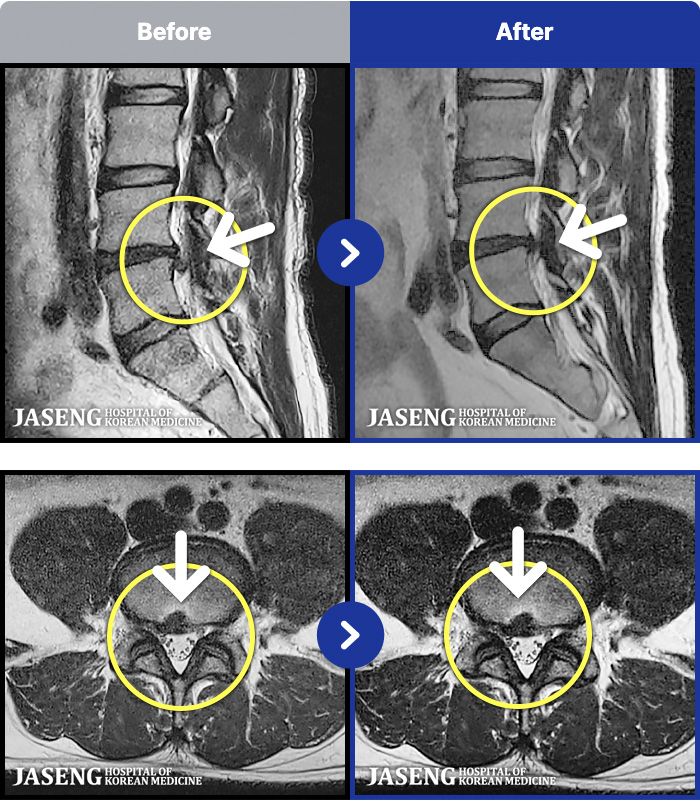

[ϻ] 24.07.25~25.08.01

ȯںп Ǹ ǿ ԿǾ, ο ġ ۿ Ƿ ġḦ Ͻñ ٶϴ.